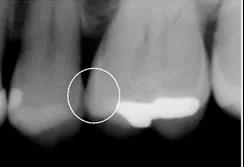

X光片

拍摄X光片显示:在X线片中未发现明显的近中邻面的低密度影像。